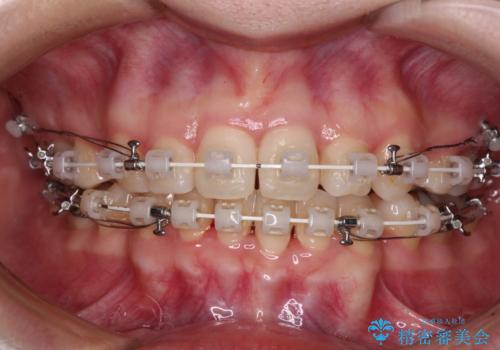

- 矯正装置

- 審美装置

上下前歯が非接触である開咬は、インビザラインによる治療がお勧めではありますが、非抜歯矯正か抜歯矯正か悩む口元であり、途中抜歯矯正に切り替えたときに対応しやすいよう、ワイヤー装置にて治療を行うこととしました。

舌の突出癖の影響もあり、非抜歯矯正で治療開始したものの口元が突出し、唇が閉じにくくなってしまったため、途中で第一小臼歯4本を抜歯ししました。